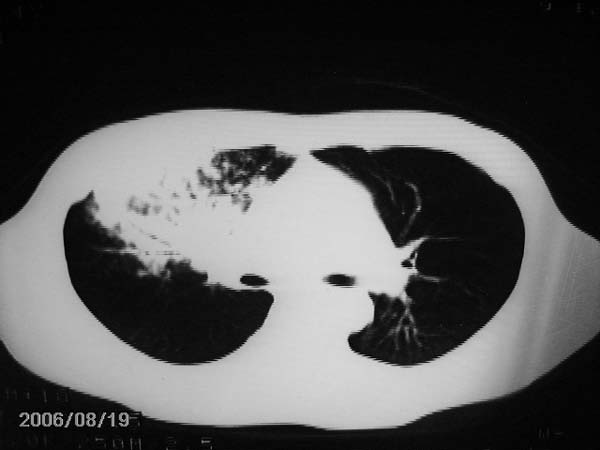

右肺中叶大片状密度增高影,内密度不均匀,右肺门处增大,应该是淋巴结肿大,结合临床首先考虑原发性肺结合可能性大,不排除合并感染可能,建议治疗后复查.

灶内密度不均,似乎有囊状,条状影,考虑右中叶综合症; 从照片中看不出有无钙化灶,若明显则考虑结核性。

考虑中叶综合征(右肺门肿大淋巴结伴中叶阻塞性炎症)